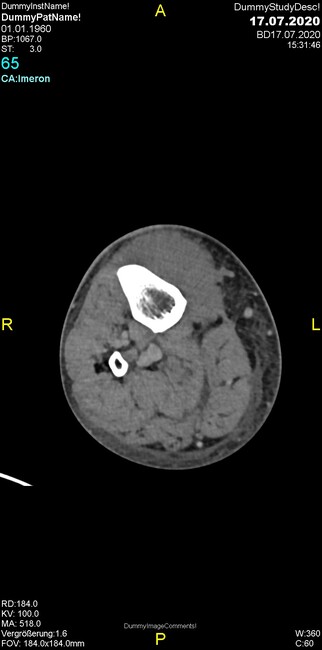

Um welche Modalitäten handelt es sich?

- Röntgen p.a. und lateral, CT coronar Knochenfenster, CT axial Weichgewebsfenster

Was fällt in der Projektionsradiographie auf?

- Verdichtung im Recessus suprapatellaris

- Aufhellungslinie in Projektion auf die Femurkondylen

- Erhöhter tibialer Slope

- Hypertransparenz tibial

- Subluxationsstellung im Kniegelenk

Was trifft auf den Befund zu?

- Der Befund beschränkt sich auf den Knochen.

- Es besteht hochakuter Handlungsbedarf.

- Der Befund ist tendenziell benigne.

- Der Befund ist tendenziell maligne.

- Der Befund weist einen Zusammenhang zum Patientenalter auf.

Was fällt in der CT im Knochenfenster auf?

- Mediale Gelenkspaltverschmälerung

- Dezente Erosion der fibulären Kortikalis

- Frakturspalt der lateralen Tibiametaphyse

- Weichgewebskalzifikationen lateral angrenzend an den Gelenkspalt

- Osteolyse der Tibiametaphyse unter Beteiligung der Kortikalis

Was kommt differentialdiagnostisch in Frage?

- Kompartmentsyndrom

- Osteomyelitis mit Weichgewebsanteil

- Metastase mit pathologischer Fraktur

- Rheumatoide Athritis

- Posttraumatische Verletzung